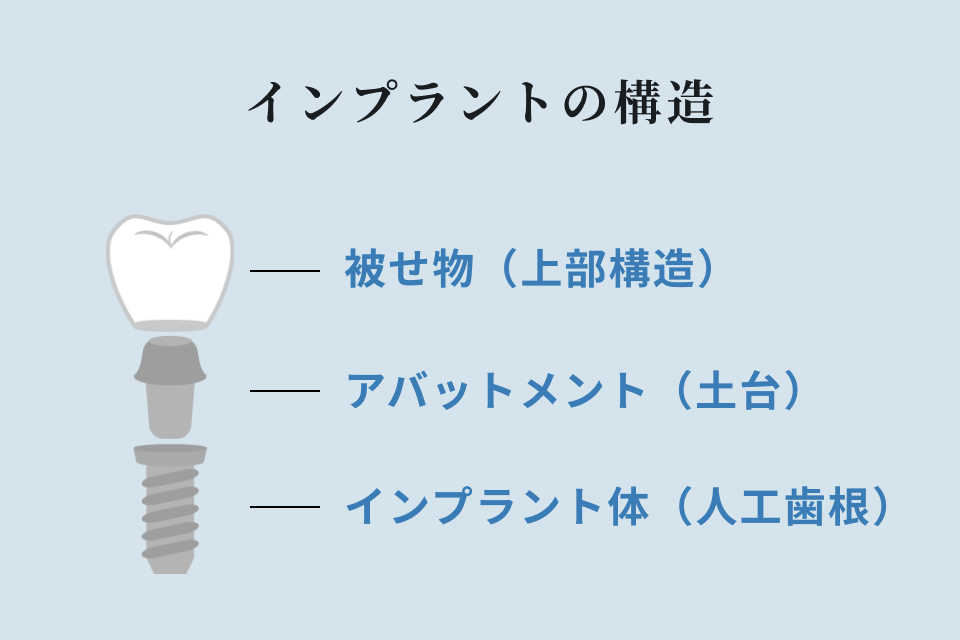

インプラントとは、虫歯や歯周病などによって、歯が抜けてしまった後の骨にインプラント(人工歯根)を埋め込み、それを土台にした歯を作る治療方法です。

歯根から再構築させるため、手術を含め処置段階が多く、治療期間も長くなりますが、入れ歯のような取り外しも不要で、ブリッジのように両隣の健康な歯を削る必要がなく、インプラント自体で力を受け止められるので残っている歯の負担を減らすことが出来ます。

見た目も自然で、ご自身の歯と同じように不自由なく噛めるようになります。